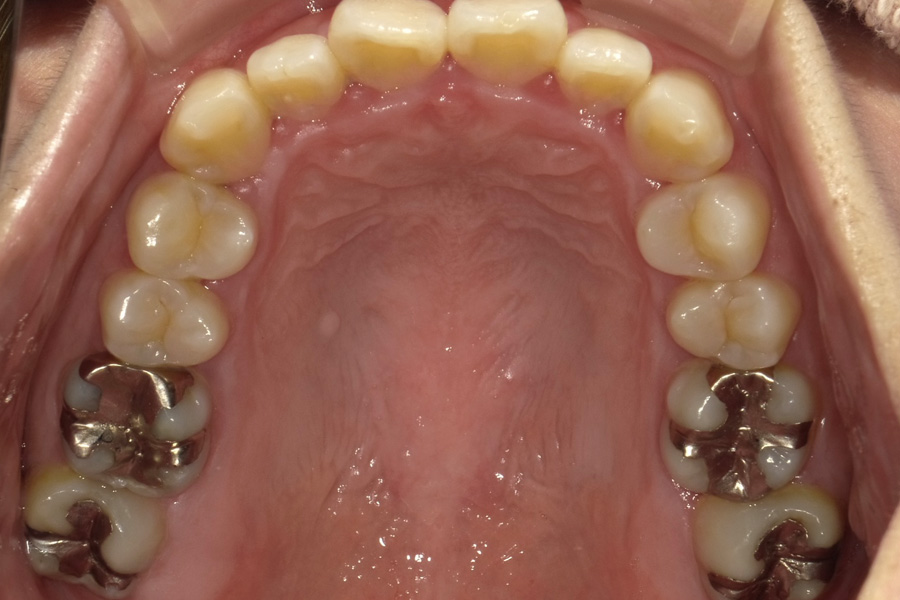

虫歯があるから削ったり悪くなったから抜くのではなく、まずは虫歯と歯周病が起きないようにより良い環境づくりをすること、そうすることによって歯を長く維持することが可能となります。

そのためには、健康状態に関する情報と生活習慣などの状況を把握したうえで、お口の中のリスク評価をおこないます。

その結果をもとに、お一人お一人にあった治療計画をご提案させていただきます。